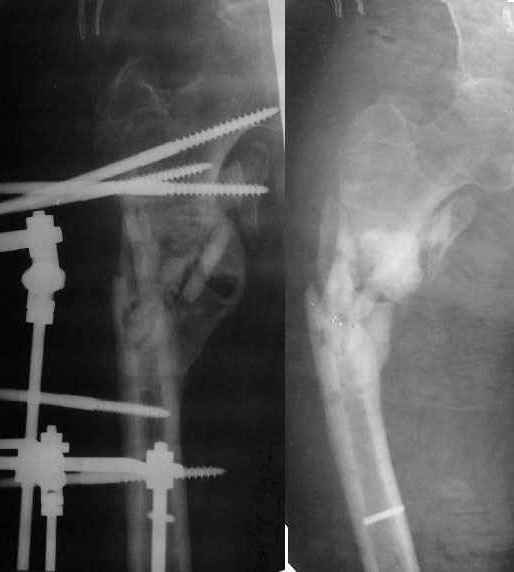

Неудачный остеосинтез пластиной: поломка винтов, миграция фиксатора. После удаления пластины сформировался гипопластический ложный сустав нижней трети бедренной кости, укорочение н/к 5 см. Выполнялся дистакционный остеосинтез аппратом Илизарова на штифте. Зона ложного сустава "не открывалась". Через 10 месяцев, когда даже регенерат полностью перестроился, консолидации в зоне ложного сустава не наступило, несмотря на стабильную фиксацию и постоянную компрессию(штифт+аппрата на 4 кольцах).

|

Неудачный остеосинтез пластиной: поломка винтов. После удаления сформирался гиполастический ложный сустав. Остеосинтез АВФ, циклическая компрессия-дистракция в области ложного сустава привела к формированию хорошей рентгенологической костной мозоли. Через 1,5 месяца ходил в аппарате без дополнительных средств опоры. Через 6 месяцев после клинической пробы - демотаж. Через 4 месяца после демонтажа - лизис костной мозоли, рецидив деформации.